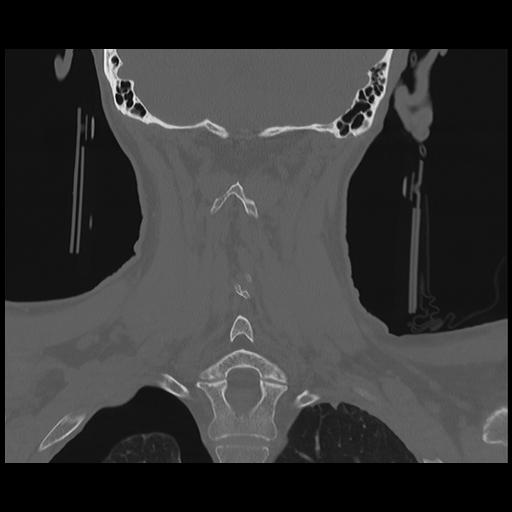

16 HUESO,,Coronal,2.000,HUESO,Coronal,